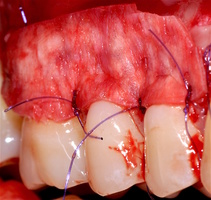

Участки 3.3-3.6 зубов и 4.3-4.6 зубов были проопери- рованы зеркально по методу коронально-ротированно- го лоскута по M. De Sanctis и G. Zucchelli (2000) с одним послабляющим вертикальным разрезом в области 3.3 зуба или 4.3 зуба.

6. Протокол хирургической операции

Протокол хирургической операции:

1. Измерены глубины рецессий (ГР), эти замеры отложены от вершин межзубных сосочков в апикальном направлении в сторону зенита рецессии.

2. Дизайн разрезов соответствует методике Zucchelli G. коронально-ротированного смещения (2000).

3. Мобилизация слизисто-надкостничного лоскута, деэпителизация анатомических сосочков, обработка поверхности корней зубов.

4. Фиксация пластического материала ТМО (dura mater) к поверхности корней зубов в области зоны создания необходимого объема прикрепленной десны.

5. Закрытие пластического материала слизисто-надкостничным лоскутом со смещением в корональном направлении, и фиксация слизисто-надкостничного лоскута швами; дополнительная фиксация зоны перемещенных и в будущем созданных мягких тканей десны в зоне рецессии десны для стабилизации результата операции.

6. Обработка поверхностей корней зубов проводилась аналогично (см. выше).